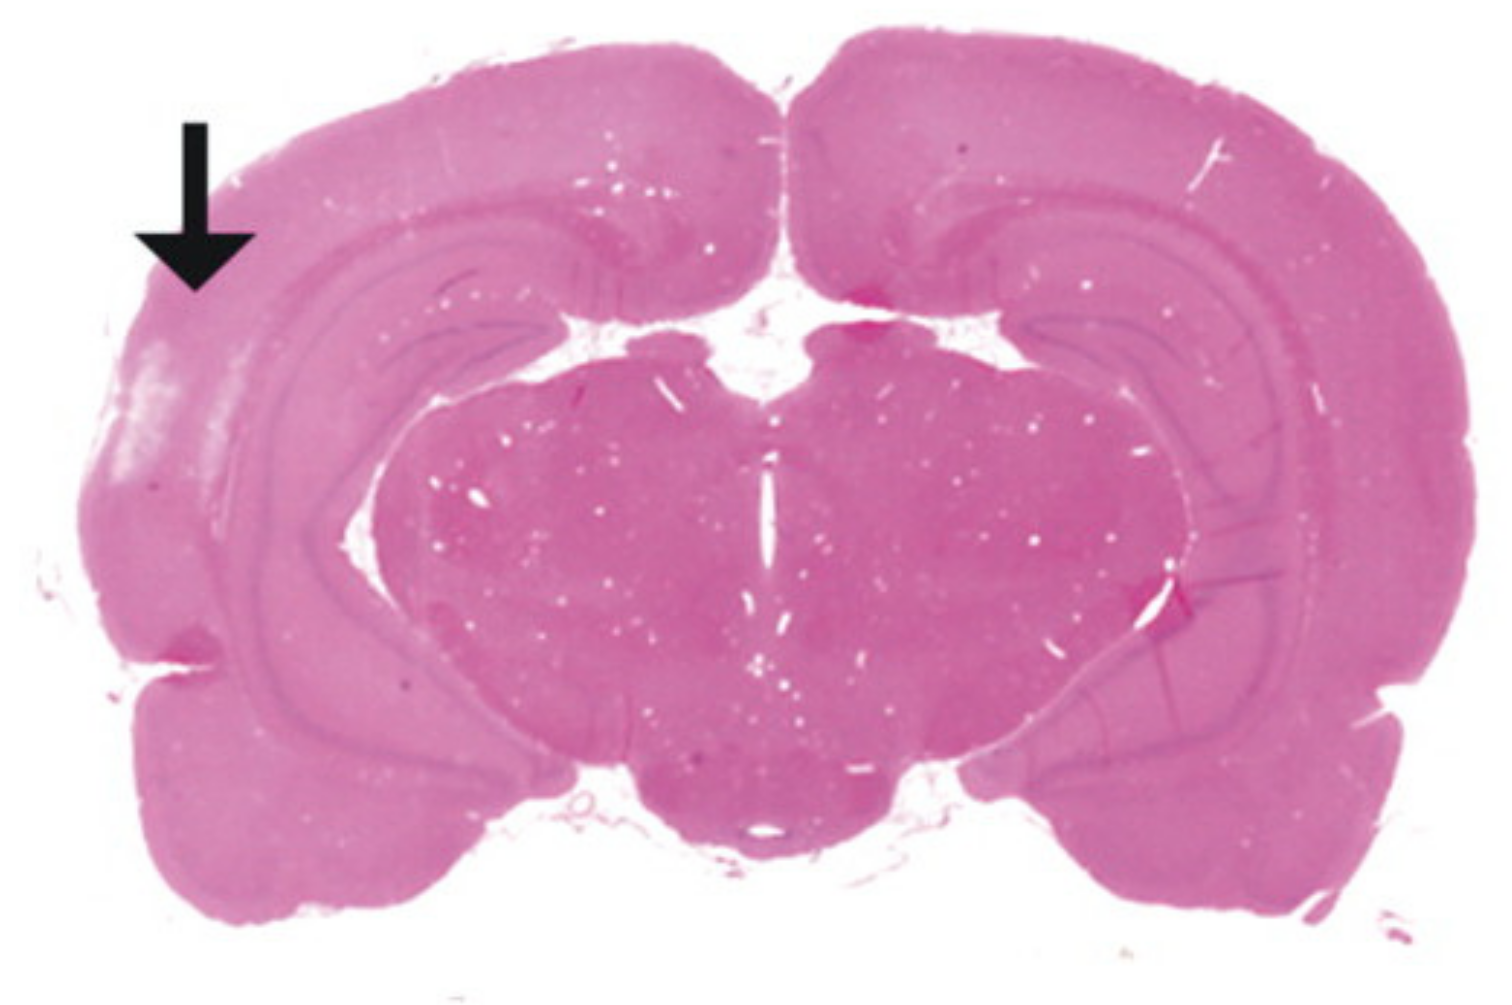

7.1. Closed-Head Impact Model of Engineered Rotational Acceleration (CHIMERA)